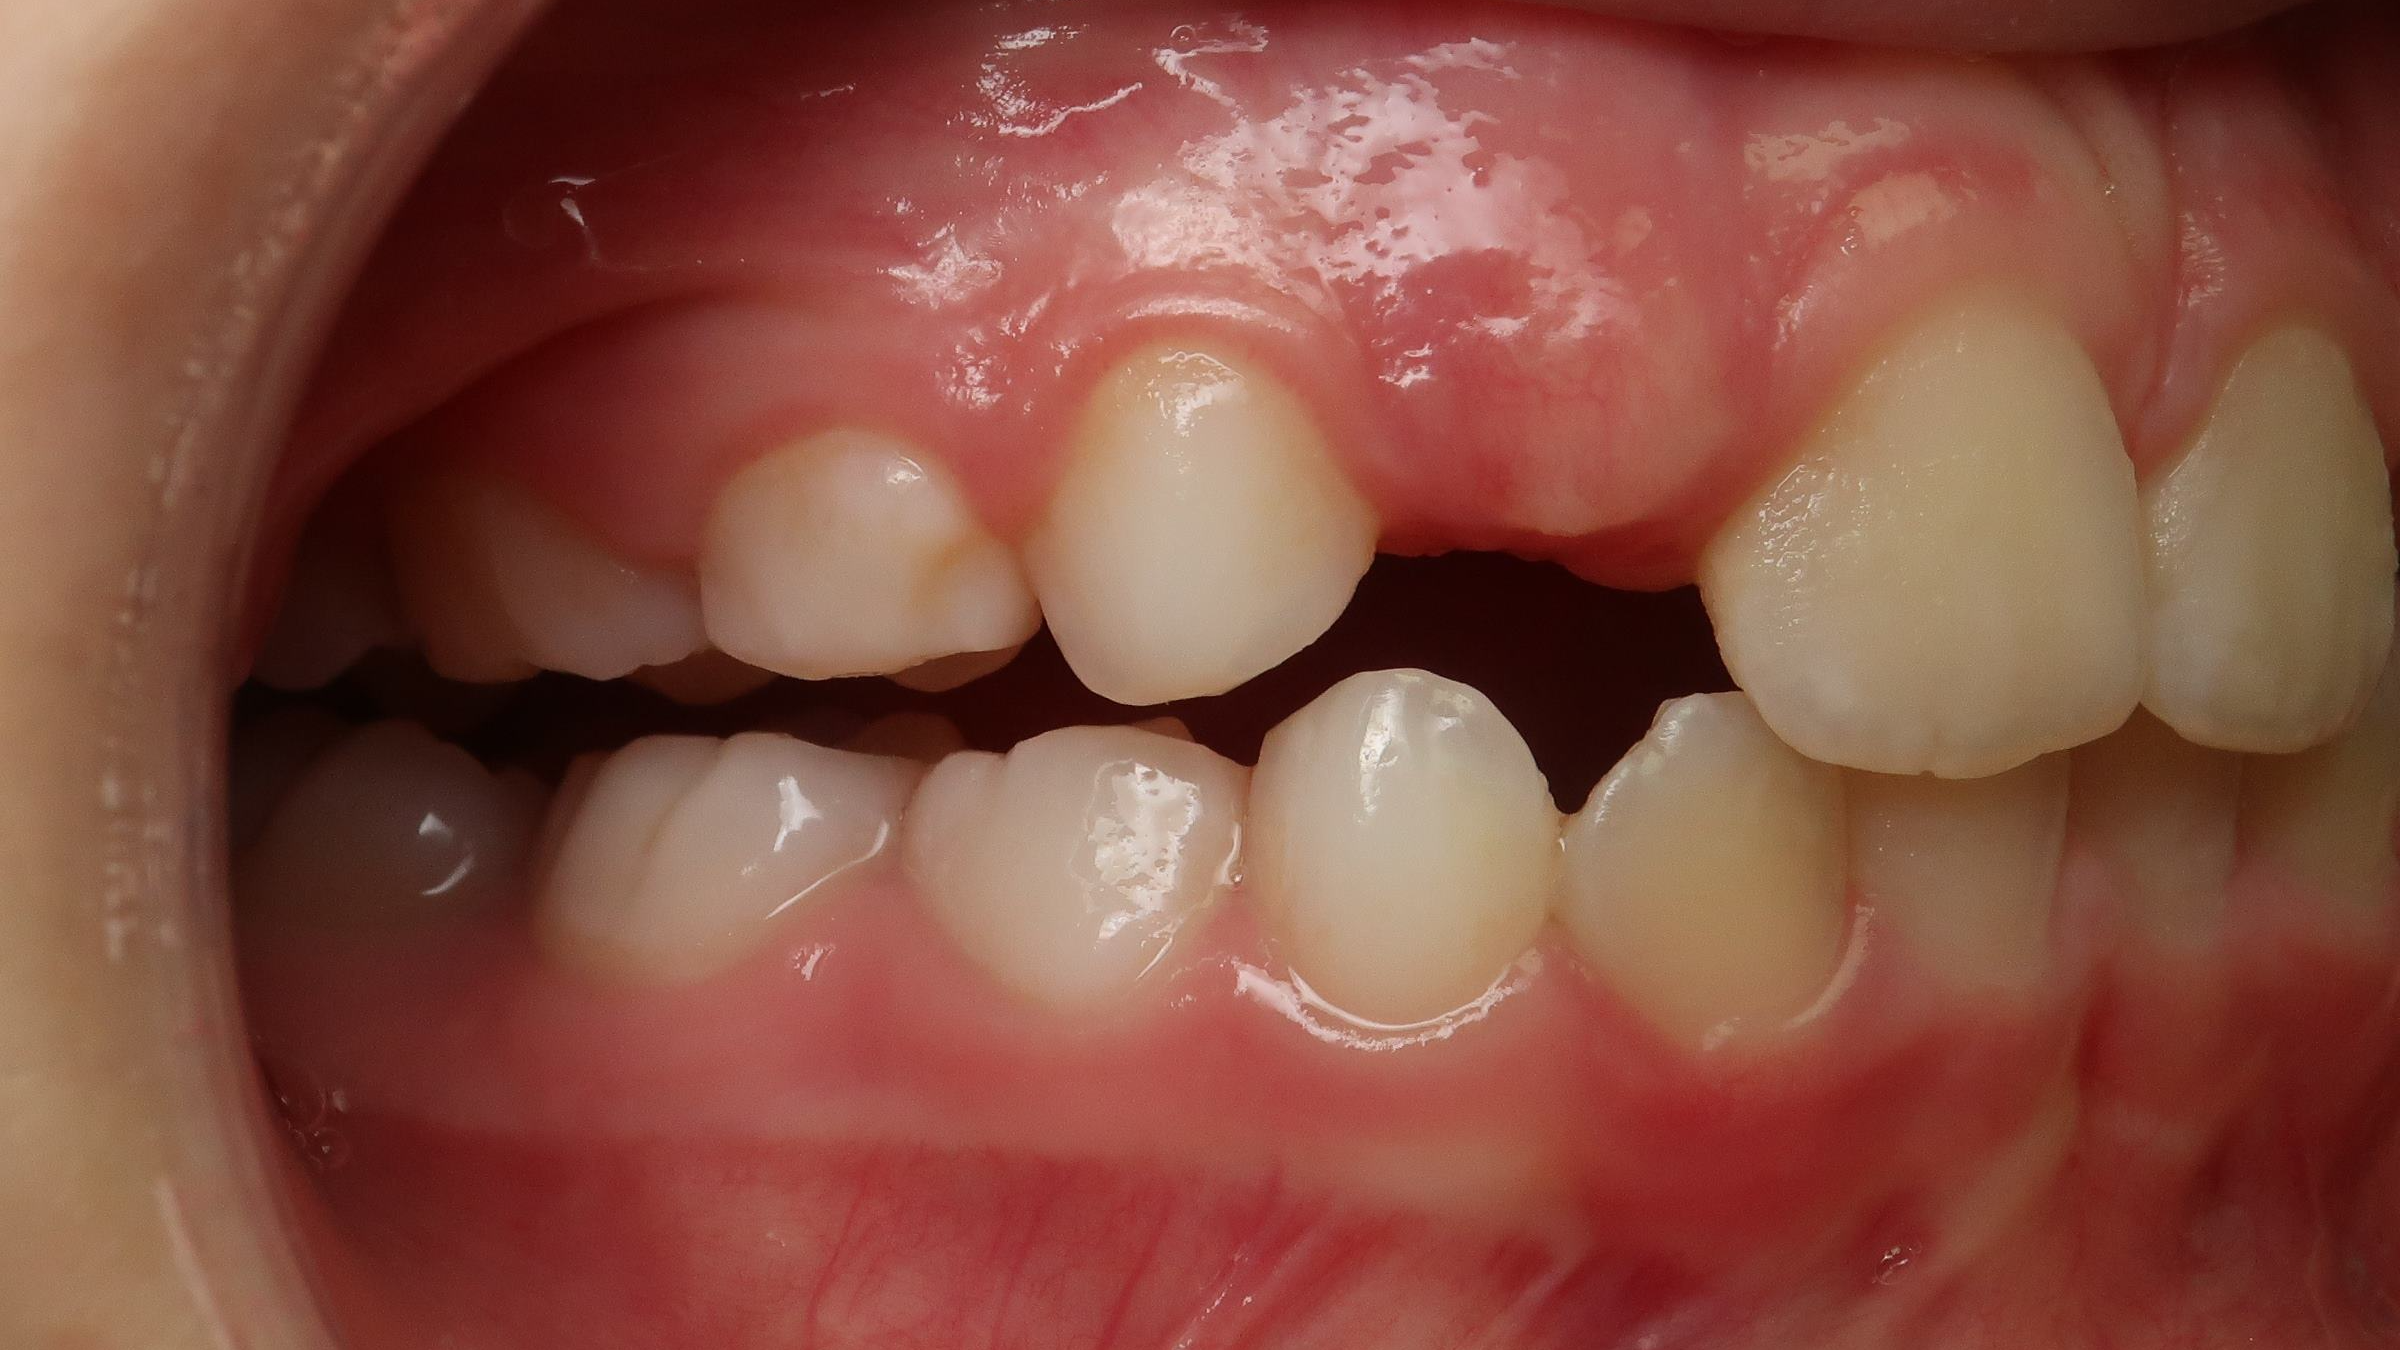

surveillance de la dentition pendant 16 mois

sectionnel multibagues pendant 24 mois

bilan début et en cours de traitement